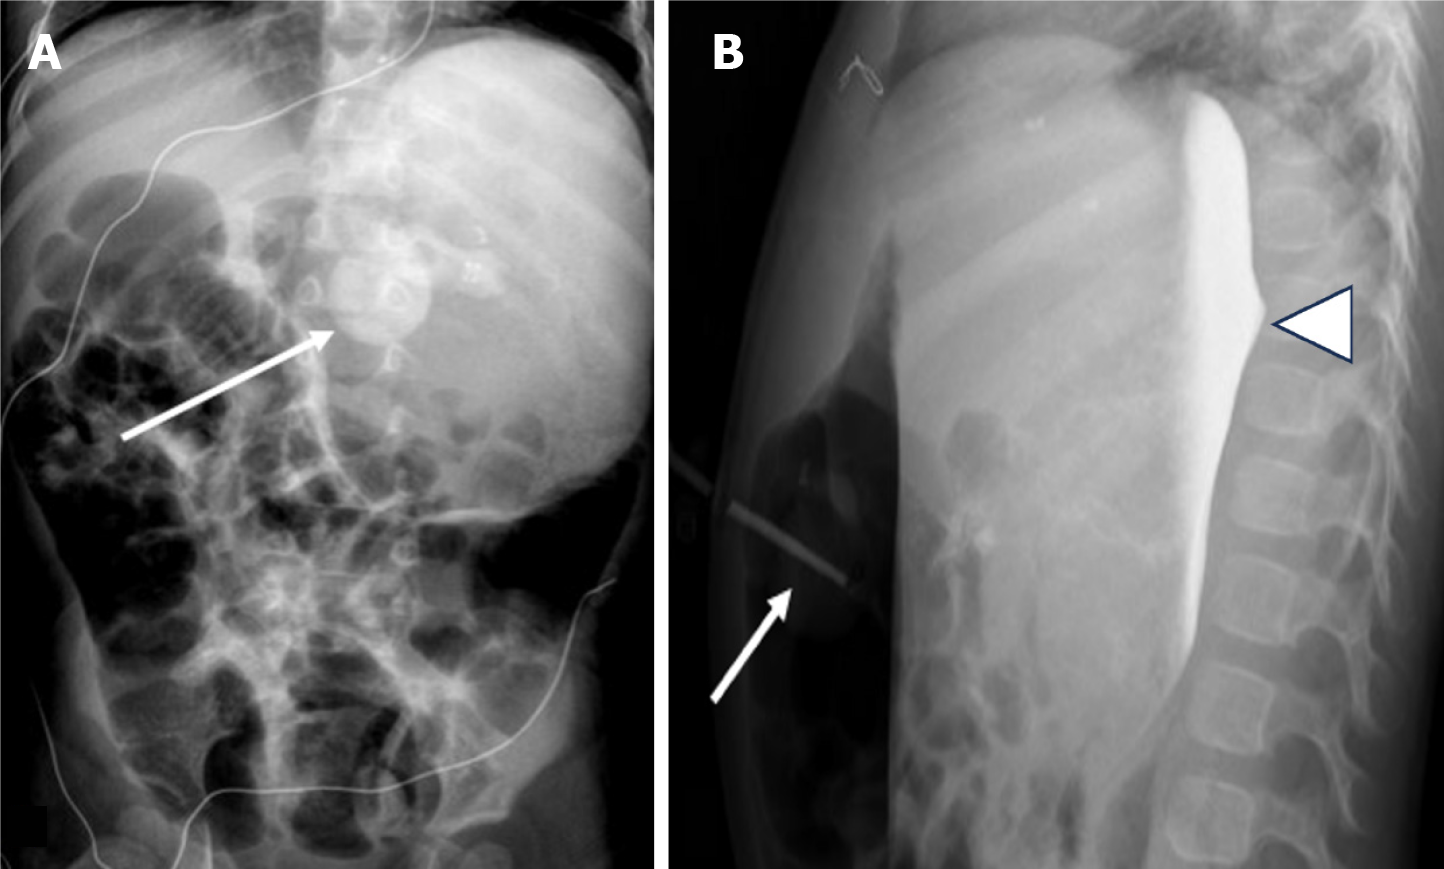

Figure 3 Free peritoneal spillage of contrast.

A: Lateral radiograph of a 1-year-old with recently exchanged tube. Injected contrast pools in the intraperitoneal cavity (arrowhead) which does not follow the stomach contour with outlining of bowel loops (arrow); B: Frontal radiograph irregular or angular margins of the injected contrast (arrow) (multiple black dots outlining the air filled stomach); C: Frontal radiograph of another 4-year-old boy demonstrates similar extrinsic outlining of bowel loops.